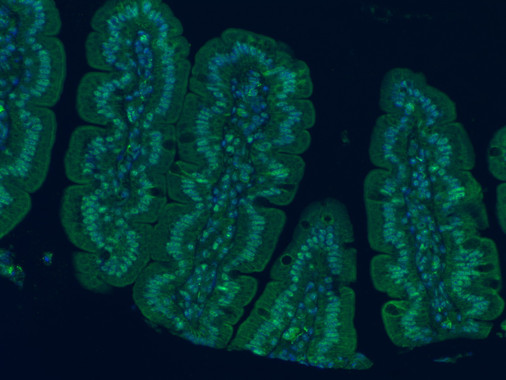

Bacterias intestinales para combatir la obesidad y el estrés

Agencia SINC Un estudio europeo coordinado por investigadores del Consejo Superior de Investigaciones Científicas (CSIC) ha demostrado que una microbiota sana contribuye a regular el apetito, el metabolismo de nutrientes como la glucosa, el peso corporal y la inflamación asociada a la obesidad. Además, también ha demostrado la influencia en el neurodesarrollo y la respuesta al estrés, que a su vez influye […]